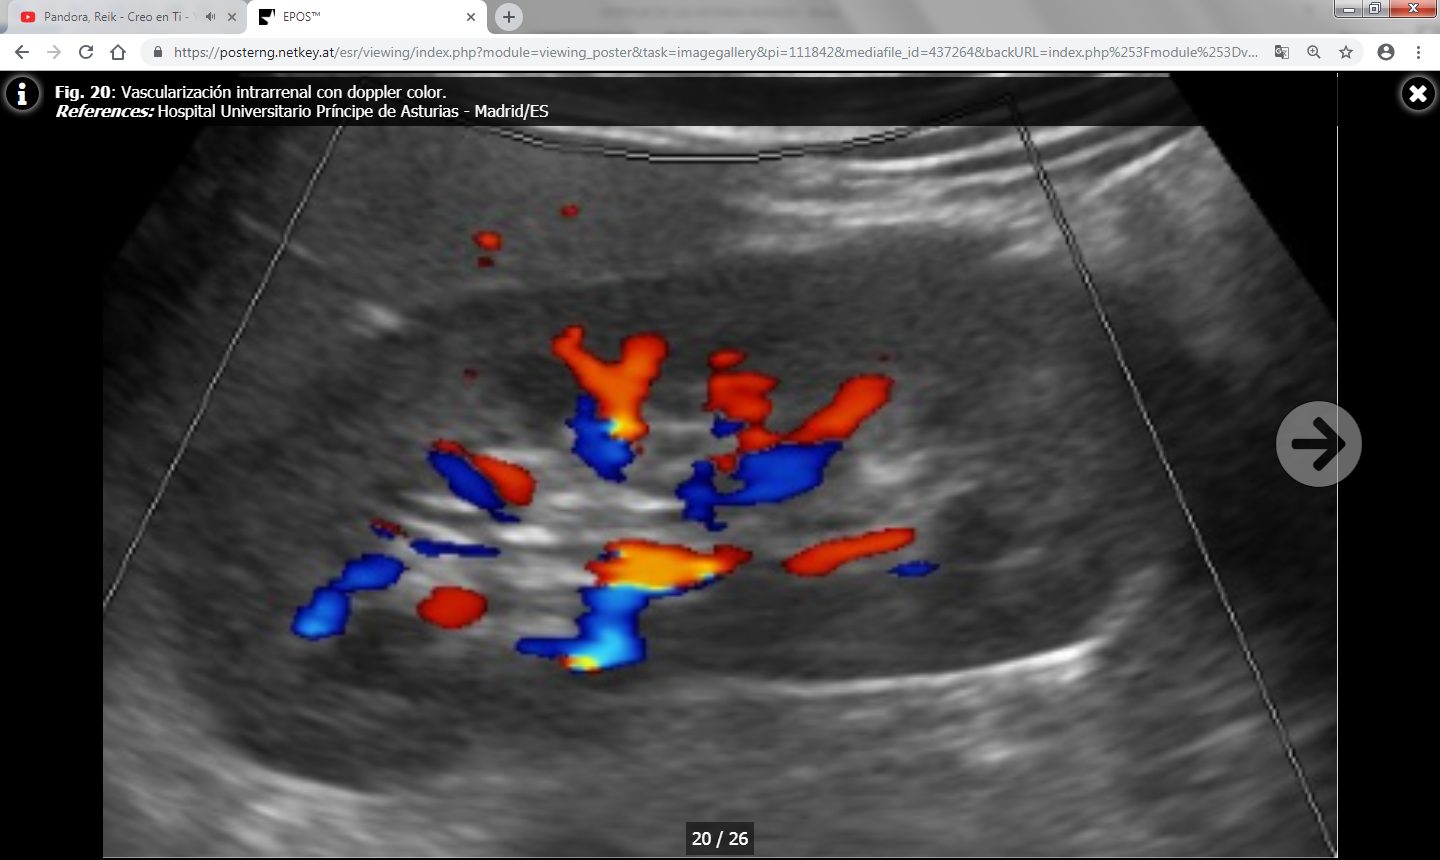

Los parámetros indirectos tienen una alta especificidad pero muy baja sensibilidad, y son los siguientes:

- Índice de resistencia (IR) : Es el resultado del cociente VPS – VTD / VPS (siendo VPS la velocidad picosistólica y VTD la velocidad al final de la diástole). Se debe calcular una media con las distintas medidas obtenidas en cada riñón y valorar si existen diferencias entre un riñón y el contralateral. Lo normal es que el índice de resistencia esté entre 0.6-0.7 y que la diferencia entre ambos riñones sea menor del 5% (ó 0.05). Un aumento de la velocidad telediastólica mayor de 150 cm/s en un paciente con IR intrarrenal menor de 0.7 es altamente sospechoso de estenosis mayor del 80%.

El IR no solamente permite detectar la presencia de estenosis significativas, sino que además predice el pronóstico y la respuesta al tratamiento de revascularización: En un estudio se publicó que en pacientes con IR mayores de 0.8 había escasa respuesta al tratamiento de revascularización ya que la enfermedad renal estaba establecida y era irreversible. No obstante, estos datos han sido ampliamente discutidos en la literatura y no existe acuerdo a día de hoy. - Tiempo de aceleración (TA) e índice de aceleración (IA) : Son parámetros más operador dependientes y por ello menos fiables que el IR. Los valores normales son menores de 0.07-0.08 ms y menores de 3 m/s respectivamente.